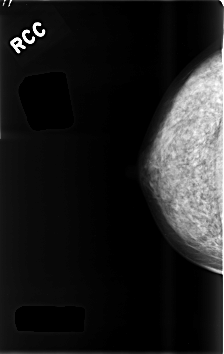

ics_version 1.0 filename C-0480-1 DATE_OF_STUDY 1 8 1994 PATIENT_AGE 44 FILM FILM_TYPE REGULAR DENSITY 3 DATE_DIGITIZED 2 2 1999 DIGITIZER LUMISYS LASER SEQUENCE LEFT_CC LINES 4536 PIXELS_PER_LINE 2912 BITS_PER_PIXEL 12 RESOLUTION 50 OVERLAY LEFT_MLO LINES 4480 PIXELS_PER_LINE 2944 BITS_PER_PIXEL 12 RESOLUTION 50 OVERLAY RIGHT_CC LINES 4592 PIXELS_PER_LINE 2904 BITS_PER_PIXEL 12 RESOLUTION 50 NON_OVERLAY RIGHT_MLO LINES 4552 PIXELS_PER_LINE 2888 BITS_PER_PIXEL 12 RESOLUTION 50 NON_OVERLAY |